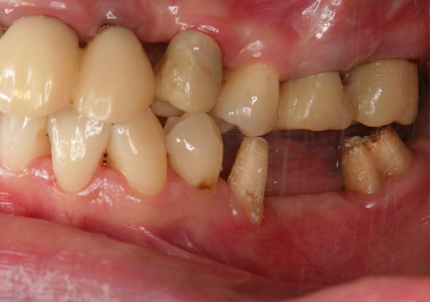

1.初診時口腔内(2007年7月31日)

主訴 ①:左下痛くて歯肉が腫れる

左下7番部ポケット7~9ミリ

左下5番部ポケット3~5ミリ

治療計画 ①:歯周病初期治療、歯周外科